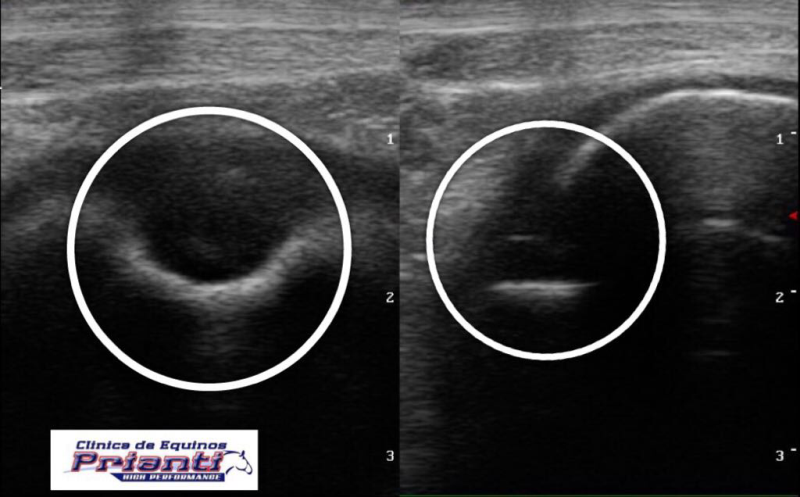

A radiografia e a ultrassonografia são os exames complementares de maior aplicação no diagnóstico de lesões císticas, a praticidade e confiabilidade dessas técnicas possibilitam o veterinário trabalhar a campo, sem emprego de grande logística.